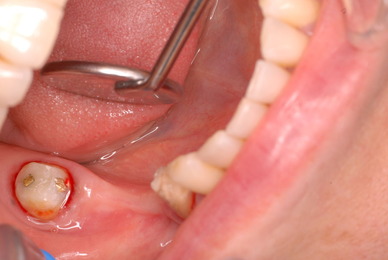

お口の中から差し歯、入れ歯、詰め物を追放しましょう!

口の中の病気を治し、病気を興さない医療を目指します。